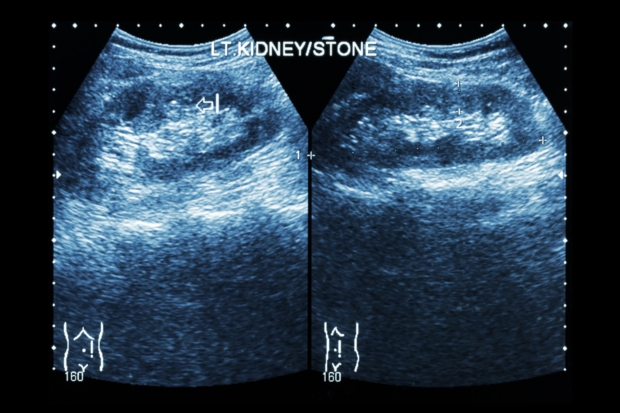

Patients with large kidney stones can benefit from alpha blockers for stone passage: Study

Patients with large kidney stones can benefit from alpha blockers for stone passage. Roughly one in 11 Americans will develop kidney stones in their lifetime. Although kidney stones can be passed while urinating, in some cases, the stones are far too large to pass through, so medical intervention must take place. In some cases, alpha ...click here to read more